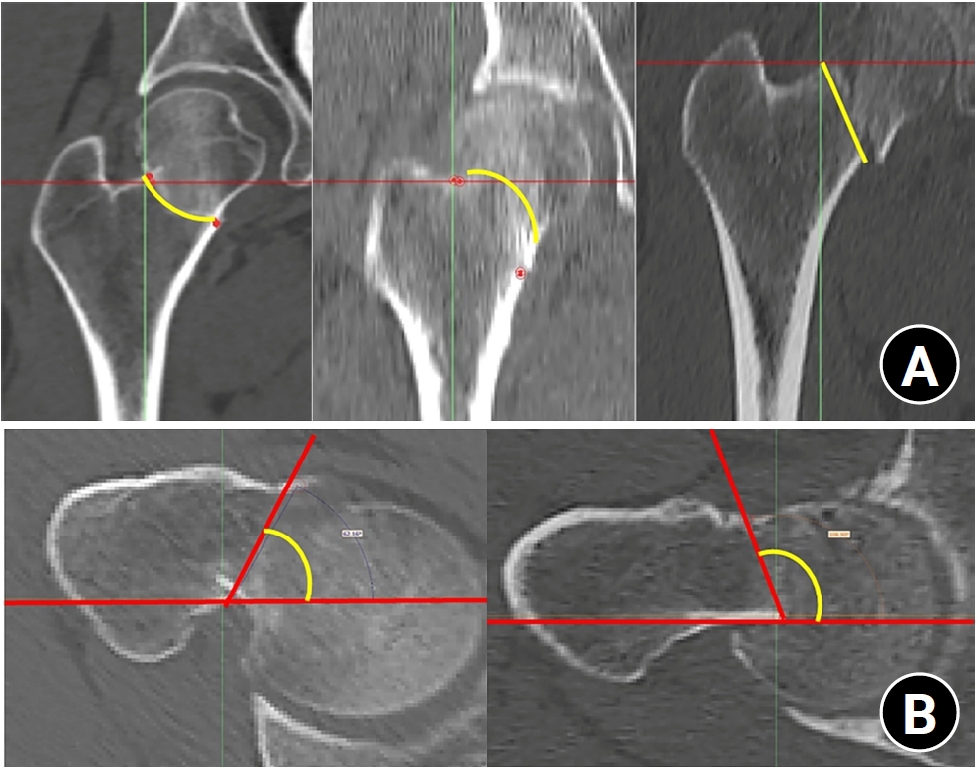

In the reformatted coronal images, the coronal PA was used to classify three types of Pauwels' (type I <30°, type II, 30°–50°, and III >50°). Based on the fracture line, the coronal morphology (coronal type) was divided into three types of linear, convex, and concave type (Fig. 3A). Concerning the axial morphology (axial type), if the angle of axial verticality was less than 90°, it was a cephalad type, and if it was more than 90°, it was a trochanteric type (Fig. 3B).

Fig. 3.

(A) In the reformatted coronal images, fractures were classified into three morphological types—linear, convex, and concave—based on the fracture line. (B) Axial verticality was classified according to the measured angle: fractures with an angle <90° were defined as the cephalad type, and those with an angle ≥90° as the trochanteric type.

Fig. 3. (A) In the reformatted coronal images, fractures were classified into three morphological types—linear, convex, and concave—based on the fracture line. (B) Axial verticality was classified according to the measured angle: fractures with an angle <90° were defined as the cephalad type, and those with an angle ≥90° as the trochanteric type.